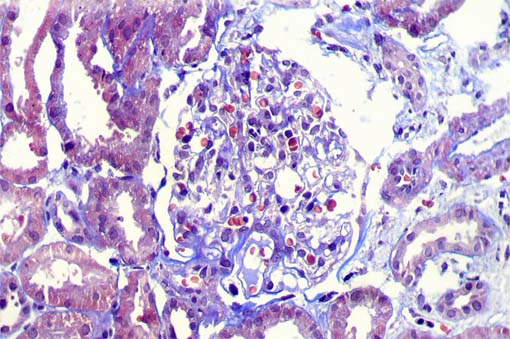

Figure 7.

Direct immunofluorescence using antiserum

to IgM, X400. Only this glomerulus showed

segmental immunostaining for IgM; other 6 glomeruli

were negative.

In total, 2 of 14 glomeruli showed segmental

lesion; both near to the tubular neck.

Direct immunofluorescence for IgA, IgG, C3 and C1q: Negative.